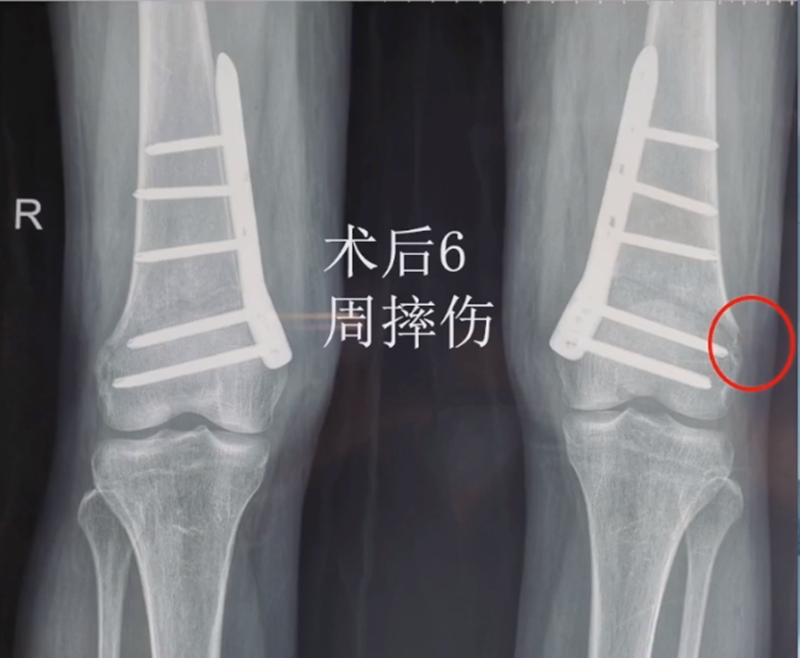

病例,X患者,女,双侧外翻膝,行双侧DFO。

术后6周摔伤,一侧出现膝内翻。

影像学检查显示左侧出现合页断裂。

进行翻修,术前力线显示内翻。